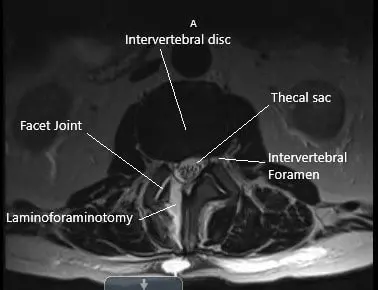

Post-operative axial MRI section showing laminoforaminotomy at L2-L3.

Postoperative sagittal MRI section of the lumbar spine showing laminoforaminotomy.